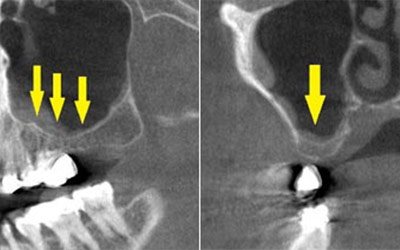

CTで見ると、骨が薄いのが良く分かります。黄色の矢印の部分、白く写るのが骨で、矢印のある黒い部分が上顎洞という空洞です。

-

この空洞部分に、人工骨を入れて、閉鎖しておくと、数か月ほどで骨に置き代わっていき、インプラントを埋入できるだけの骨量になります。サイナスリフトが終了して、数か月経過し、薄かった骨が十分な厚みができたCT画像です。黄色矢印の部分、白く写る骨が増えています。

サイナスリフトを行って、8か月後に、インプラントの埋入手術を行いました。骨が十分にあったので、通常の長さのインプラントが埋入できました。